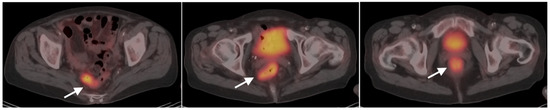

10. Anal Carcinoma